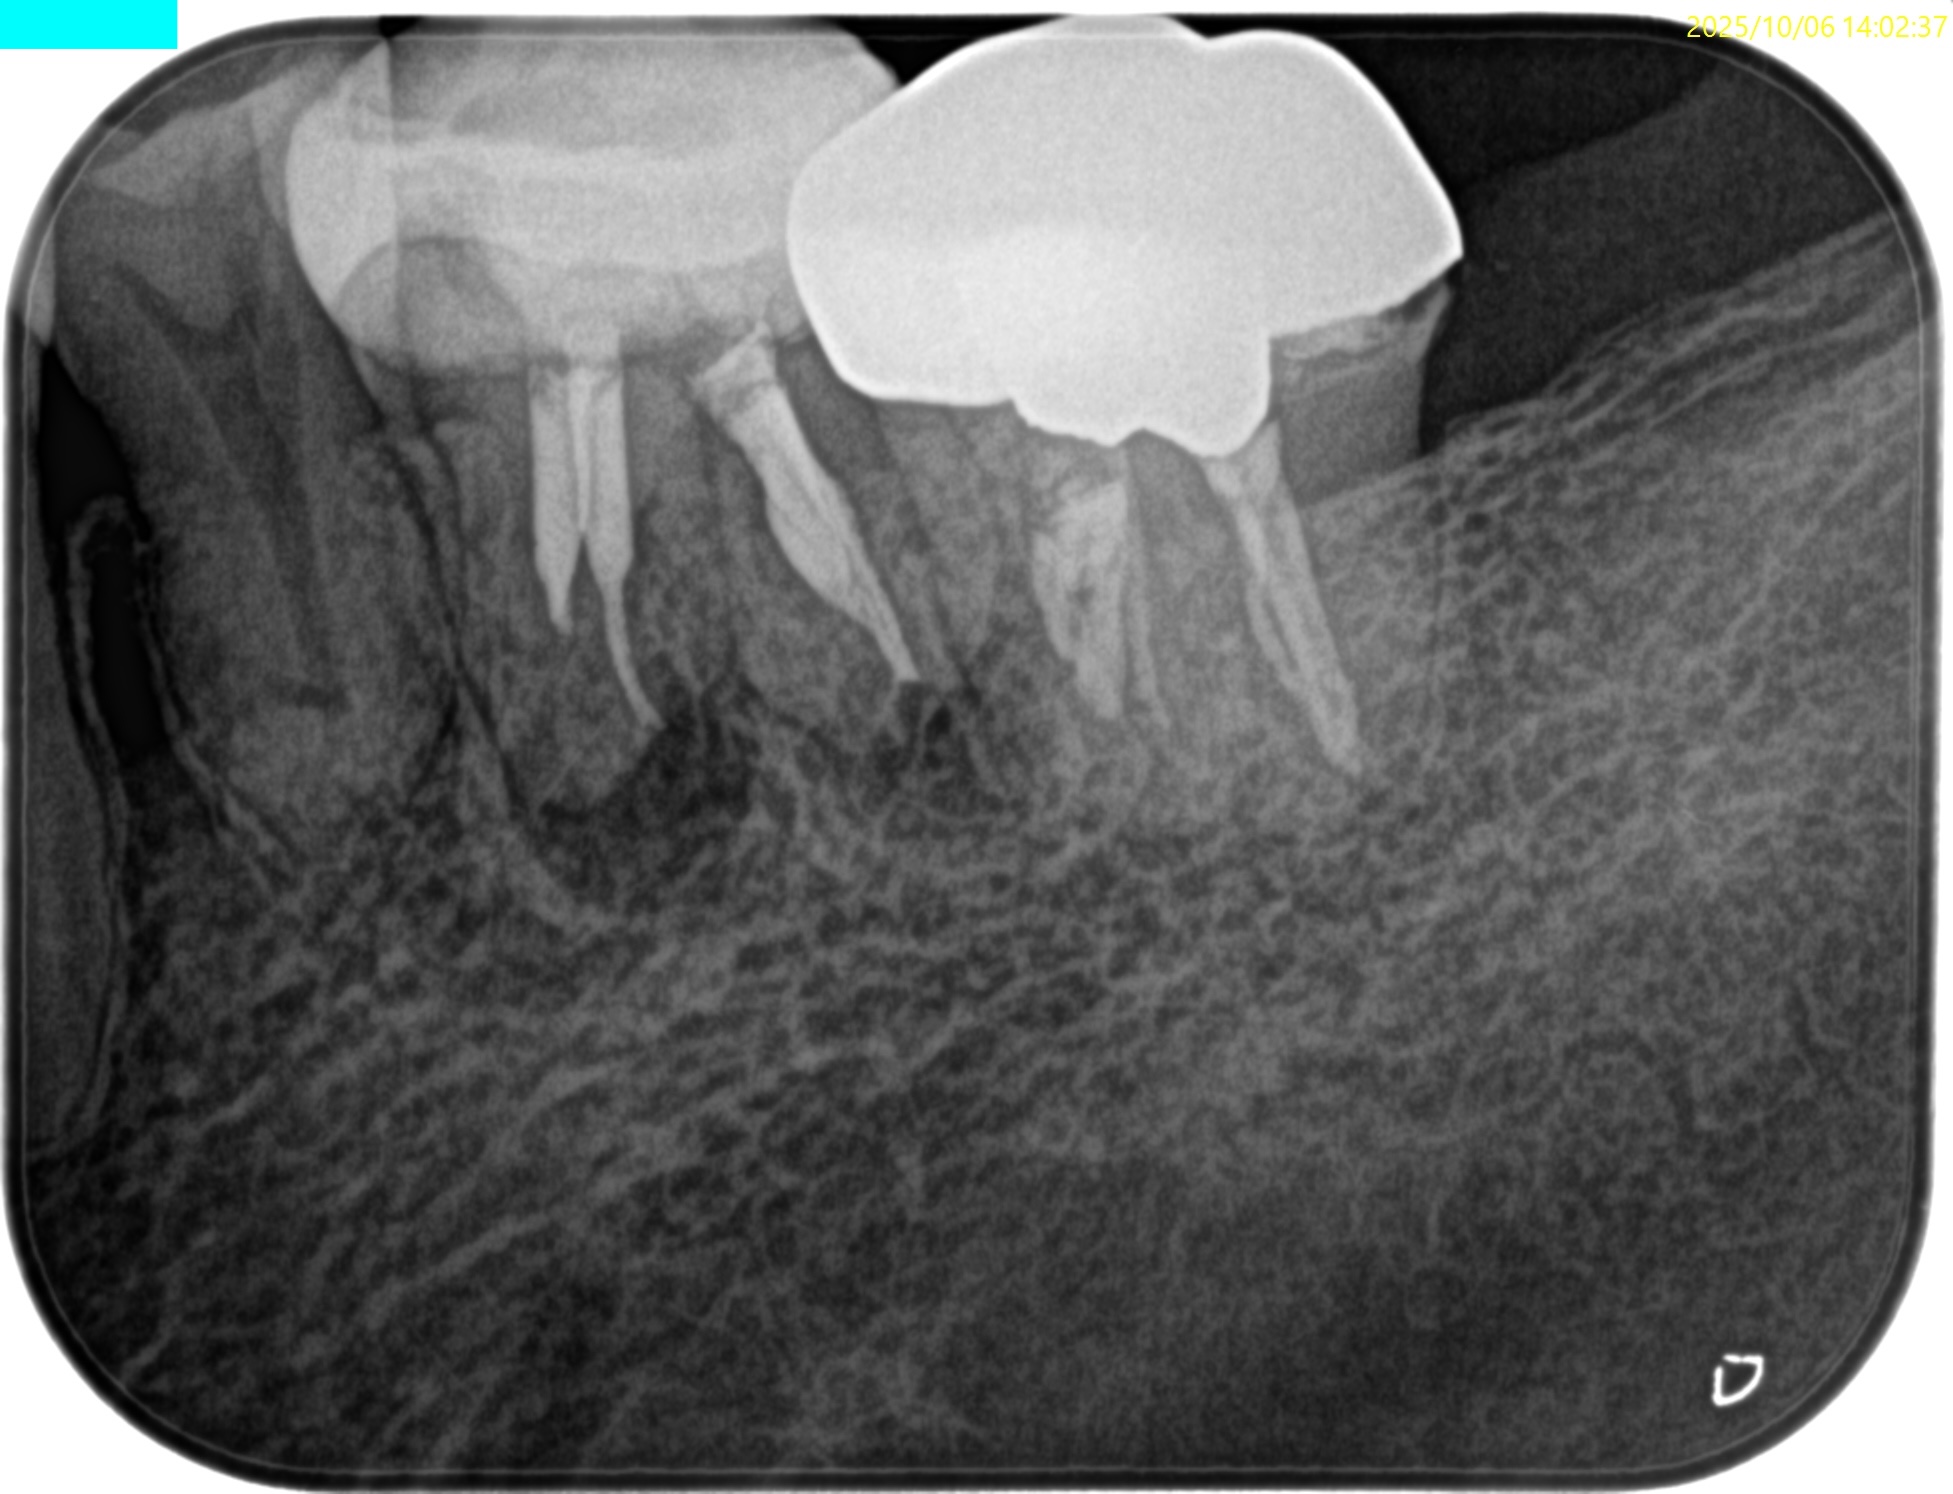

PA(2025.9.16)

CBCT(2025.9.16)

MB

ML

D

MにもDにも病変がある。

B

頬側の骨がない。

これが圧痛に対する反応の原因だ。